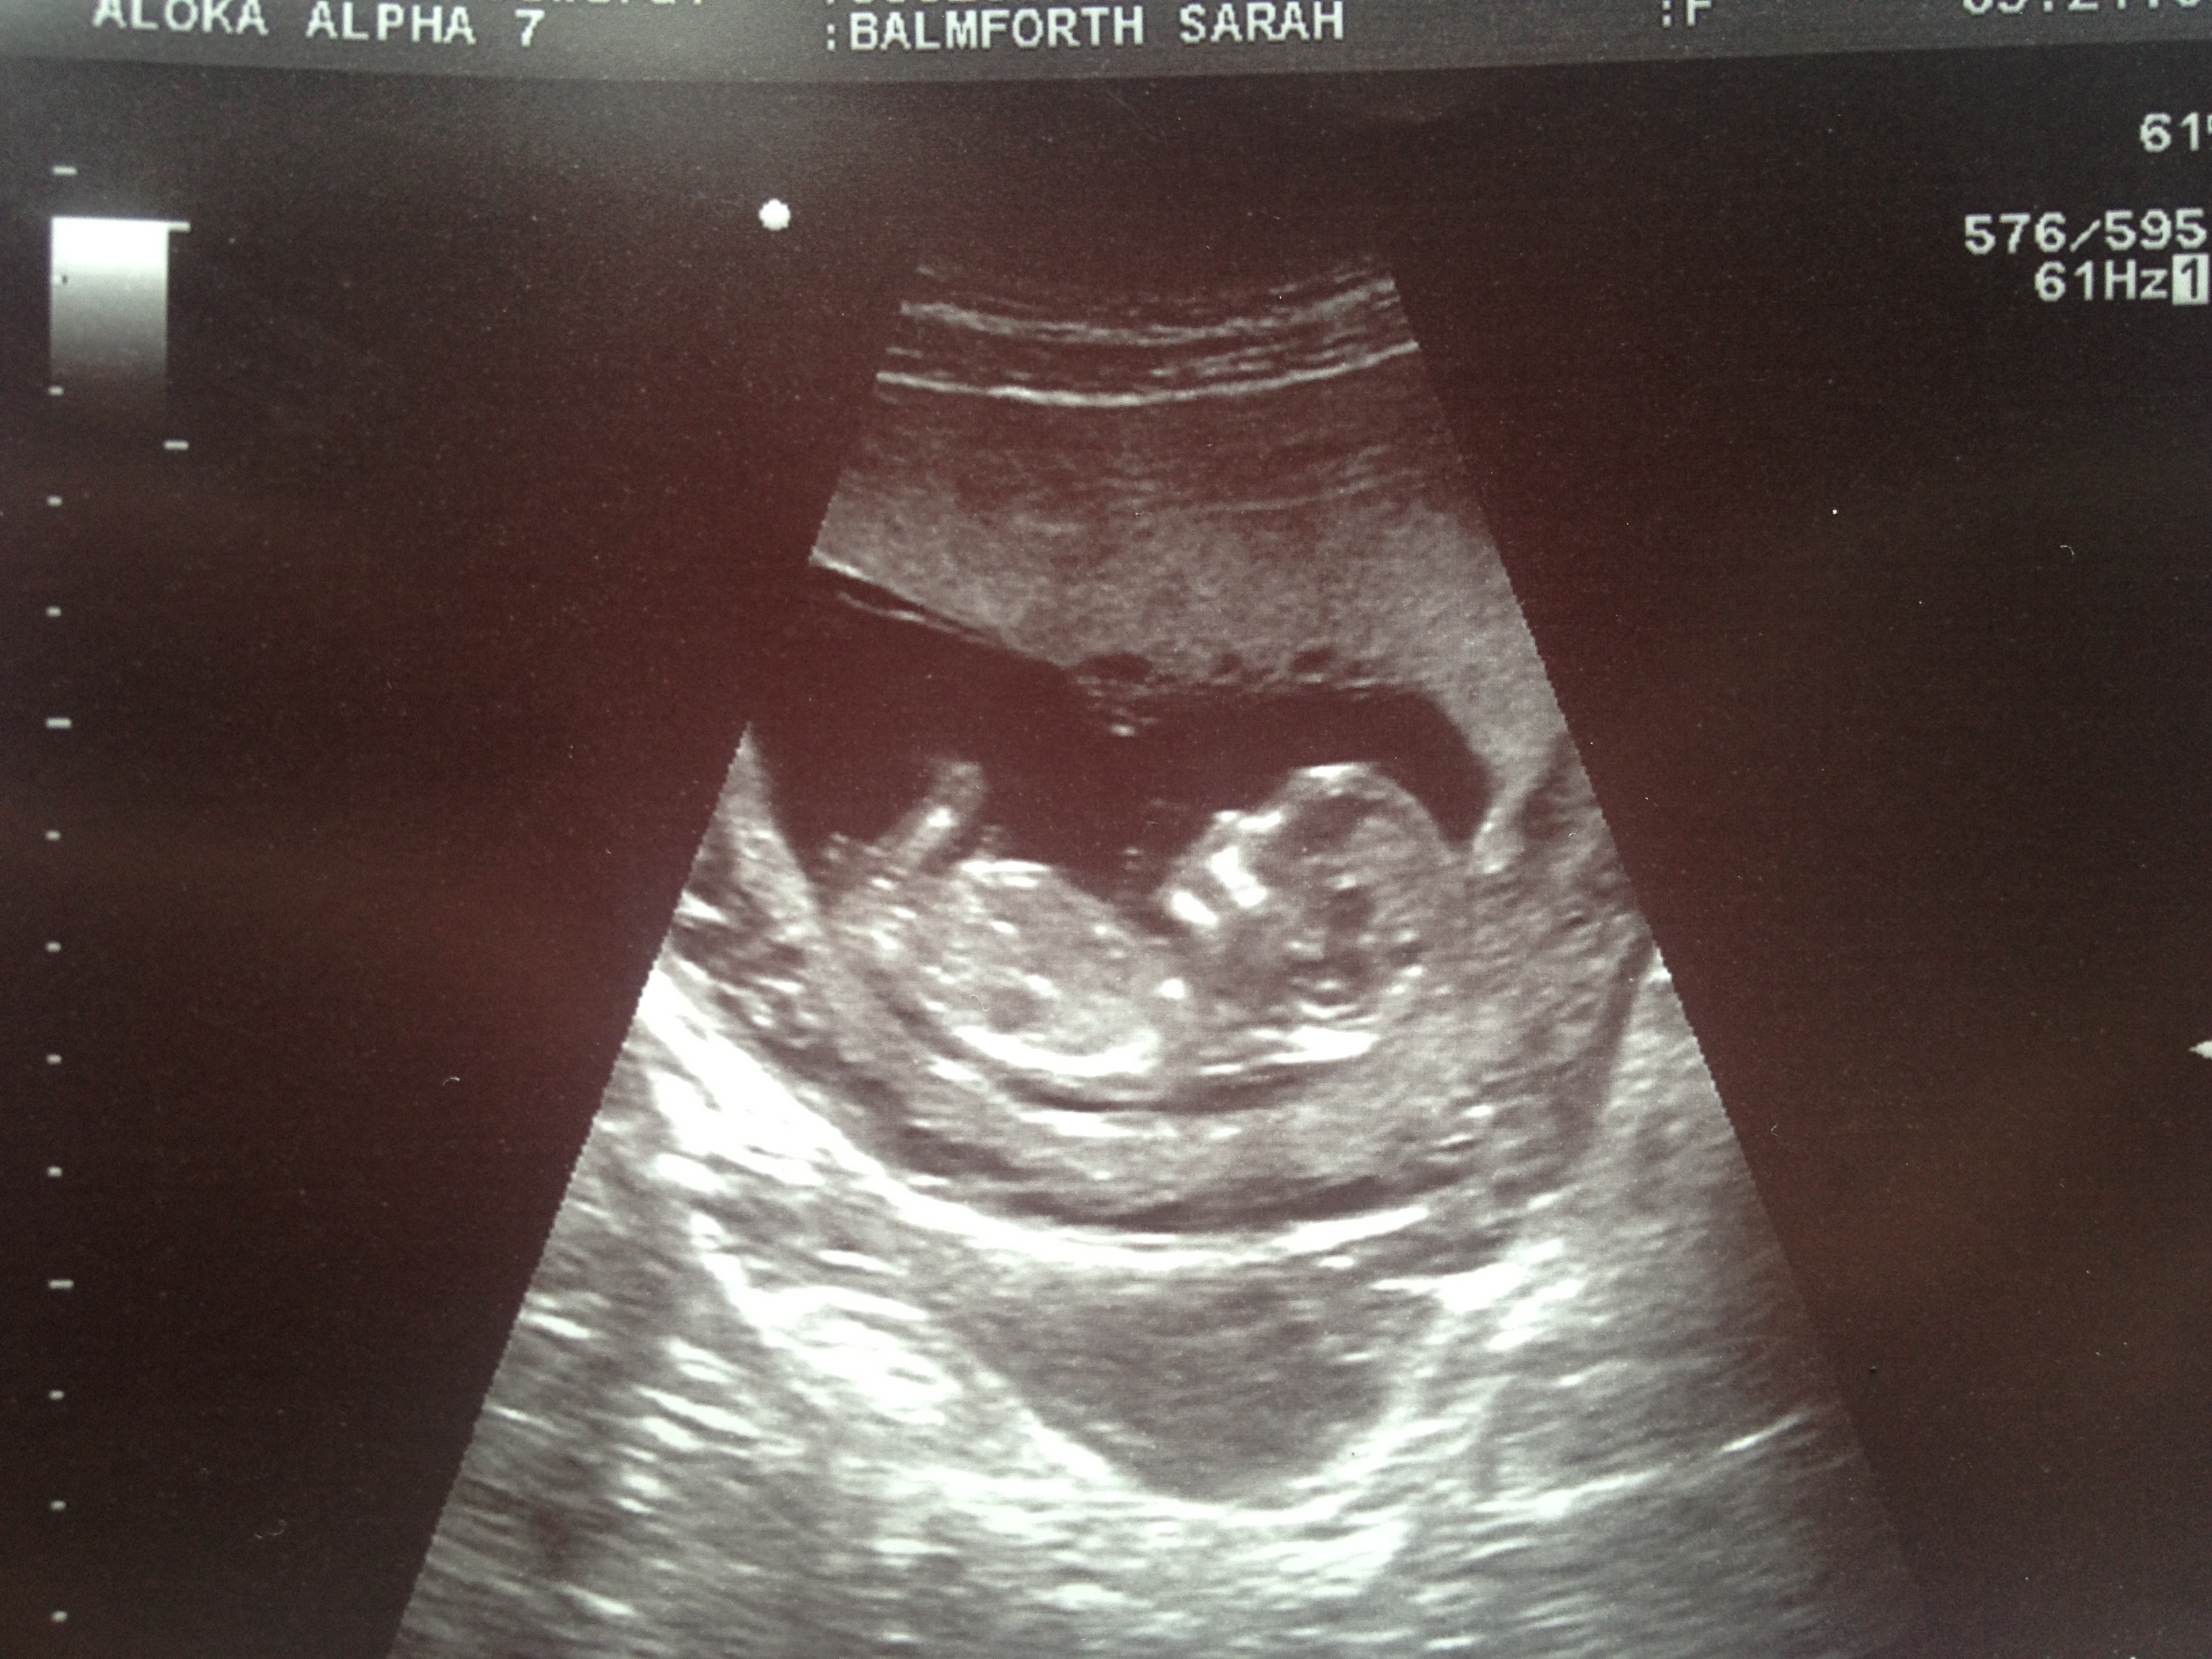

I habe another photo if anyone else would like to take a guess?Attachment 14134

I don't see a nub but maybe girl because of the differences in skull from your little boy's pic to your new pic. I'm not sure what I'm seeing in the second pic as the leg is in the way.

If that's the nub in the second pic you posted then I'm guessing girl :) x